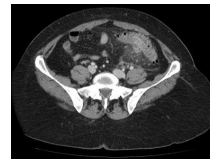

Homem 66 anos, dor em abdome inferior e febre. Leuco – 17.100. Analisando a TC de abdome abaixo, podemos identificar

Enunciado 4728801-1